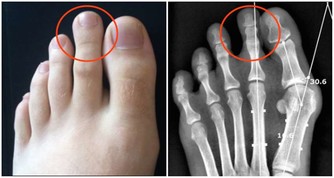

4、少吃麵食

一些關節炎患者對饅頭、麵包等麵食特別敏感,很多患者發現,不吃麵食之後,關節疼痛明顯好轉。